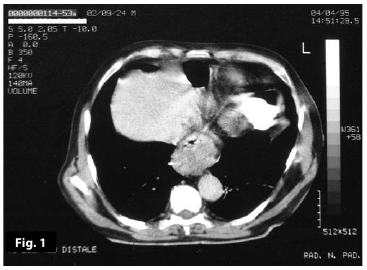

Figure1

Figure1-2

Figure1-2-3-4